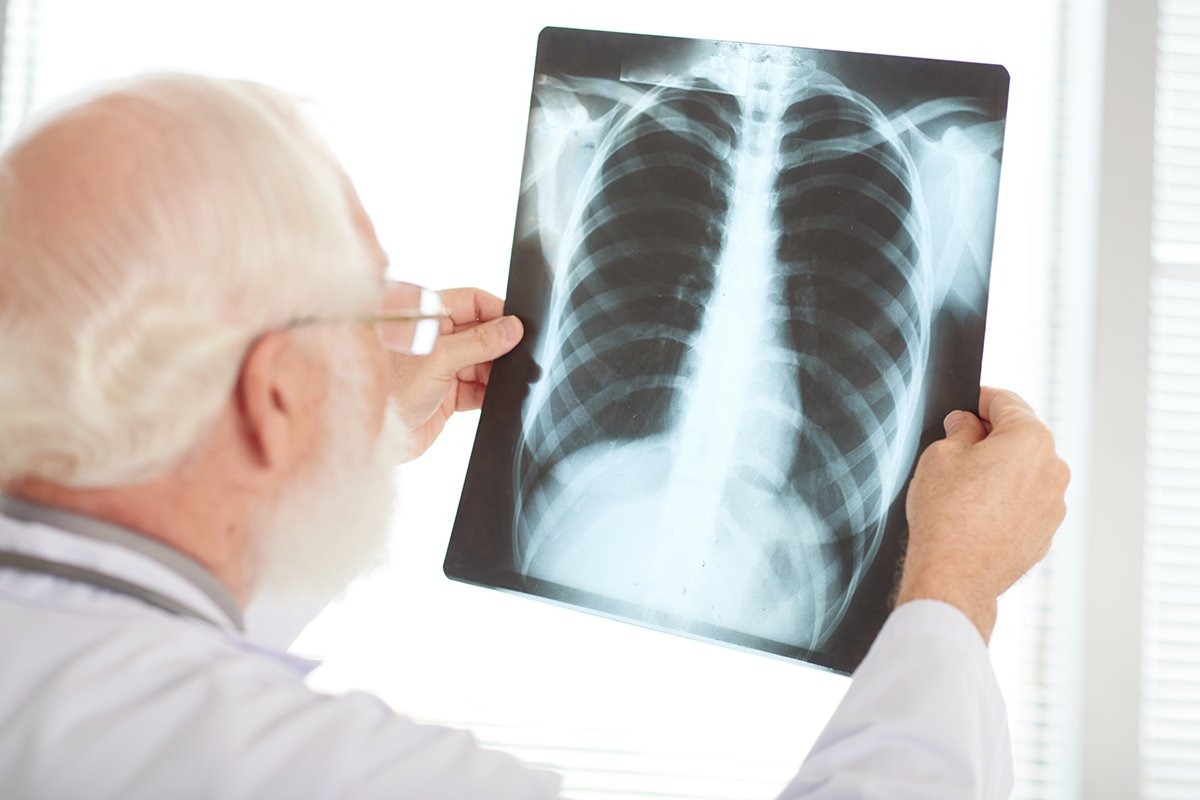

Upala pluća (pneumonija) je ozbiljna infekcija pluća, bez obzira na to da li zahvata jedno ili oba plućna krila. Kada su zahvaćena oba pluća, riječ je o obostranoj upali pluća, koja može imati teži tok i, ukoliko se ne liječi, dovesti do ozbiljnih komplikacija.

Obostrana pneumonija je infekcija koja zahvata oba plućna krila, a mogu je uzrokovati bakterije, virusi ili gljivice. Što je veći dio plućnog tkiva zahvaćen, to je klinička slika obično teža.